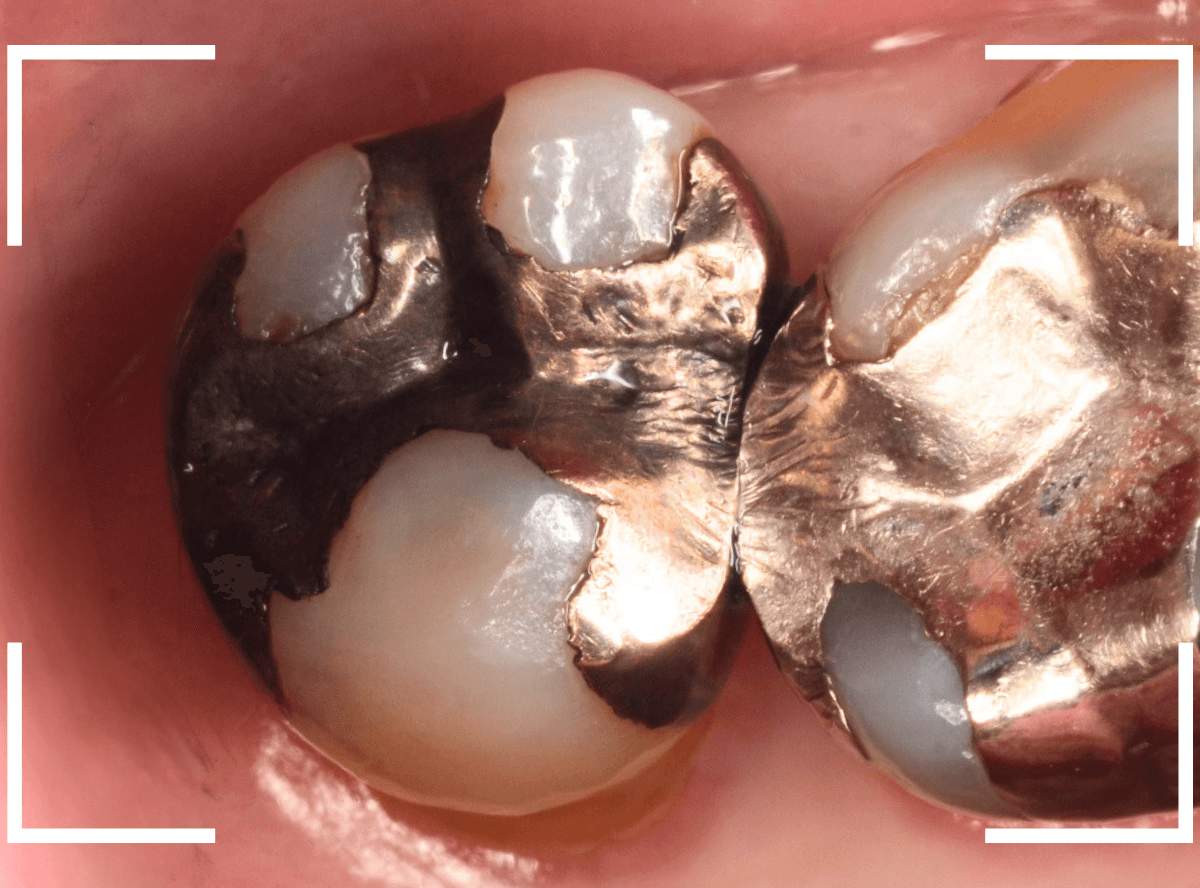

Case.14 インレーの下の歯肉まで広がった虫歯

「下の奥歯が噛むと痛む」という症状で来院された患者さんのケースです。

お口の中の状態を確認すると、奥歯の端に穴が開いているのが見えます。

ここかな?

レントゲン写真で確認します。

やはり、奥歯の端が大きな虫歯になっています。

青いラインが歯の神経、赤いラインが虫歯です。

レントゲン写真上では虫歯が神経まで達しているように見えます。

これは、神経を取らないとダメかもしれません。